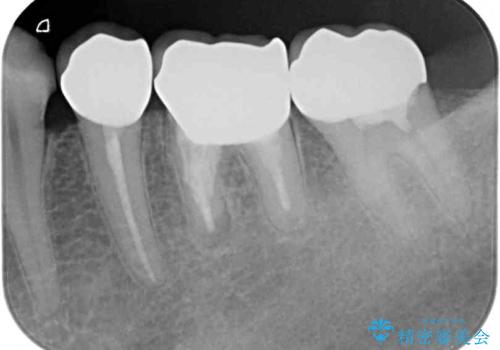

他にも、奥歯の銀歯の下にもむし歯が多くあり、痛みが生じていたため、根管治療などを行った上で、オールセラミッククラウンにて補綴治療することとしました。